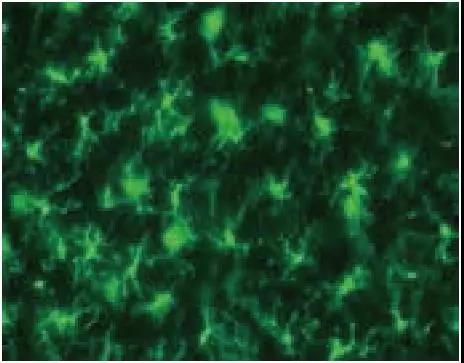

大鼠原代混合培养细胞双染色和相同视野的相位图像

绿色:Iba1(小胶质细胞)红色:GFAP(星形胶质细胞)